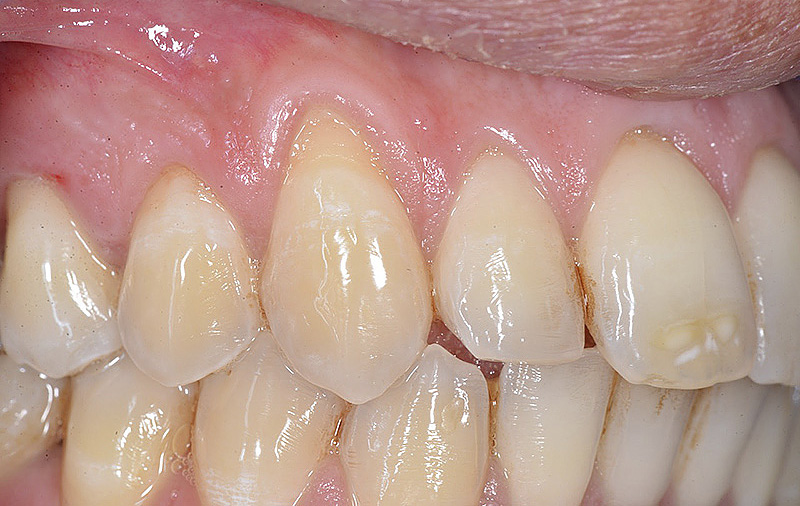

PREMESSA: in seguito all’estrazione dell’incisivo laterale superiore di destra, resasi necessaria per cause batteriche, si decide di affrontare il caso con il posizionamento di un impianto in sostituzione dell’elemento mancante dopo guarigione del sito infetto. Con tecniche rigenerative sia dei tessuti ossei mancanti a causa dell’infezione pregressa, sia dei tessuti gengivali che appaiono inizialmente troppo spostati in alto, si ripristina una corretta morfologia delle parabole (contorni) gengivali e delle papille interdentali (triangoli di gengiva tra due denti vicini).

Vengono utilizzati 2 tipi di provvisori: il primo, cementato ai denti vicini, viene utilizzato dal momento dell’estrazione del dente fino ad impianto osteointegrato (circa 6 mesi); il secondo, avvitato direttamente all’impianto, ha una funzione di prova estetica ma soprattutto di guida per la maturazione dei tessuti gengivali peri-implantari portandoli verso la maturazione completa prima di posizionare la corona finale in disilicato di litio.